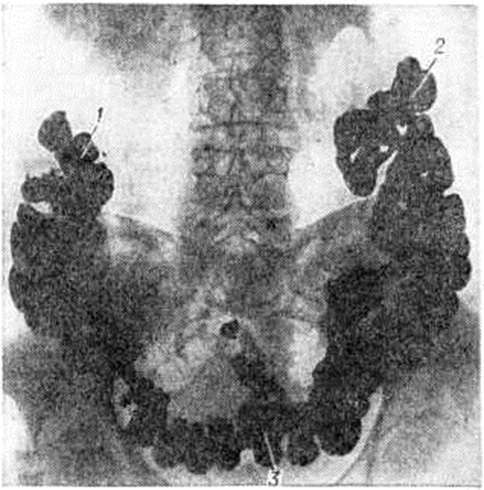

При опущении толстой кишки определяется низкое положение печеночного и селезеночного её изгибов, а также слепой и поперечной ободочной кишок. При этом чрезмерно подвижная слепая кишка может находиться в малом тазу, куда нередко провисает и имеющая вид гирлянды поперечная ободочная кишка (рисунок 3). Рельеф слизистой оболочки остаётся нормальным. Смещаемость кишки при отсутствии спаек не нарушена. В опущенной и удлиненной кишке могут наблюдаться дополнительные петли, перегибы, повышение или понижение тонуса, замедление пассажа содержимого. Задержка контрастного содержимого может достигать 96 часов и более. Опущение отделов кишечника необходимо дифференцировать с их вторичным смещением, обусловленным объемным или рубцово-спаечным процессом в брюшной полости или забрюшинном пространстве.